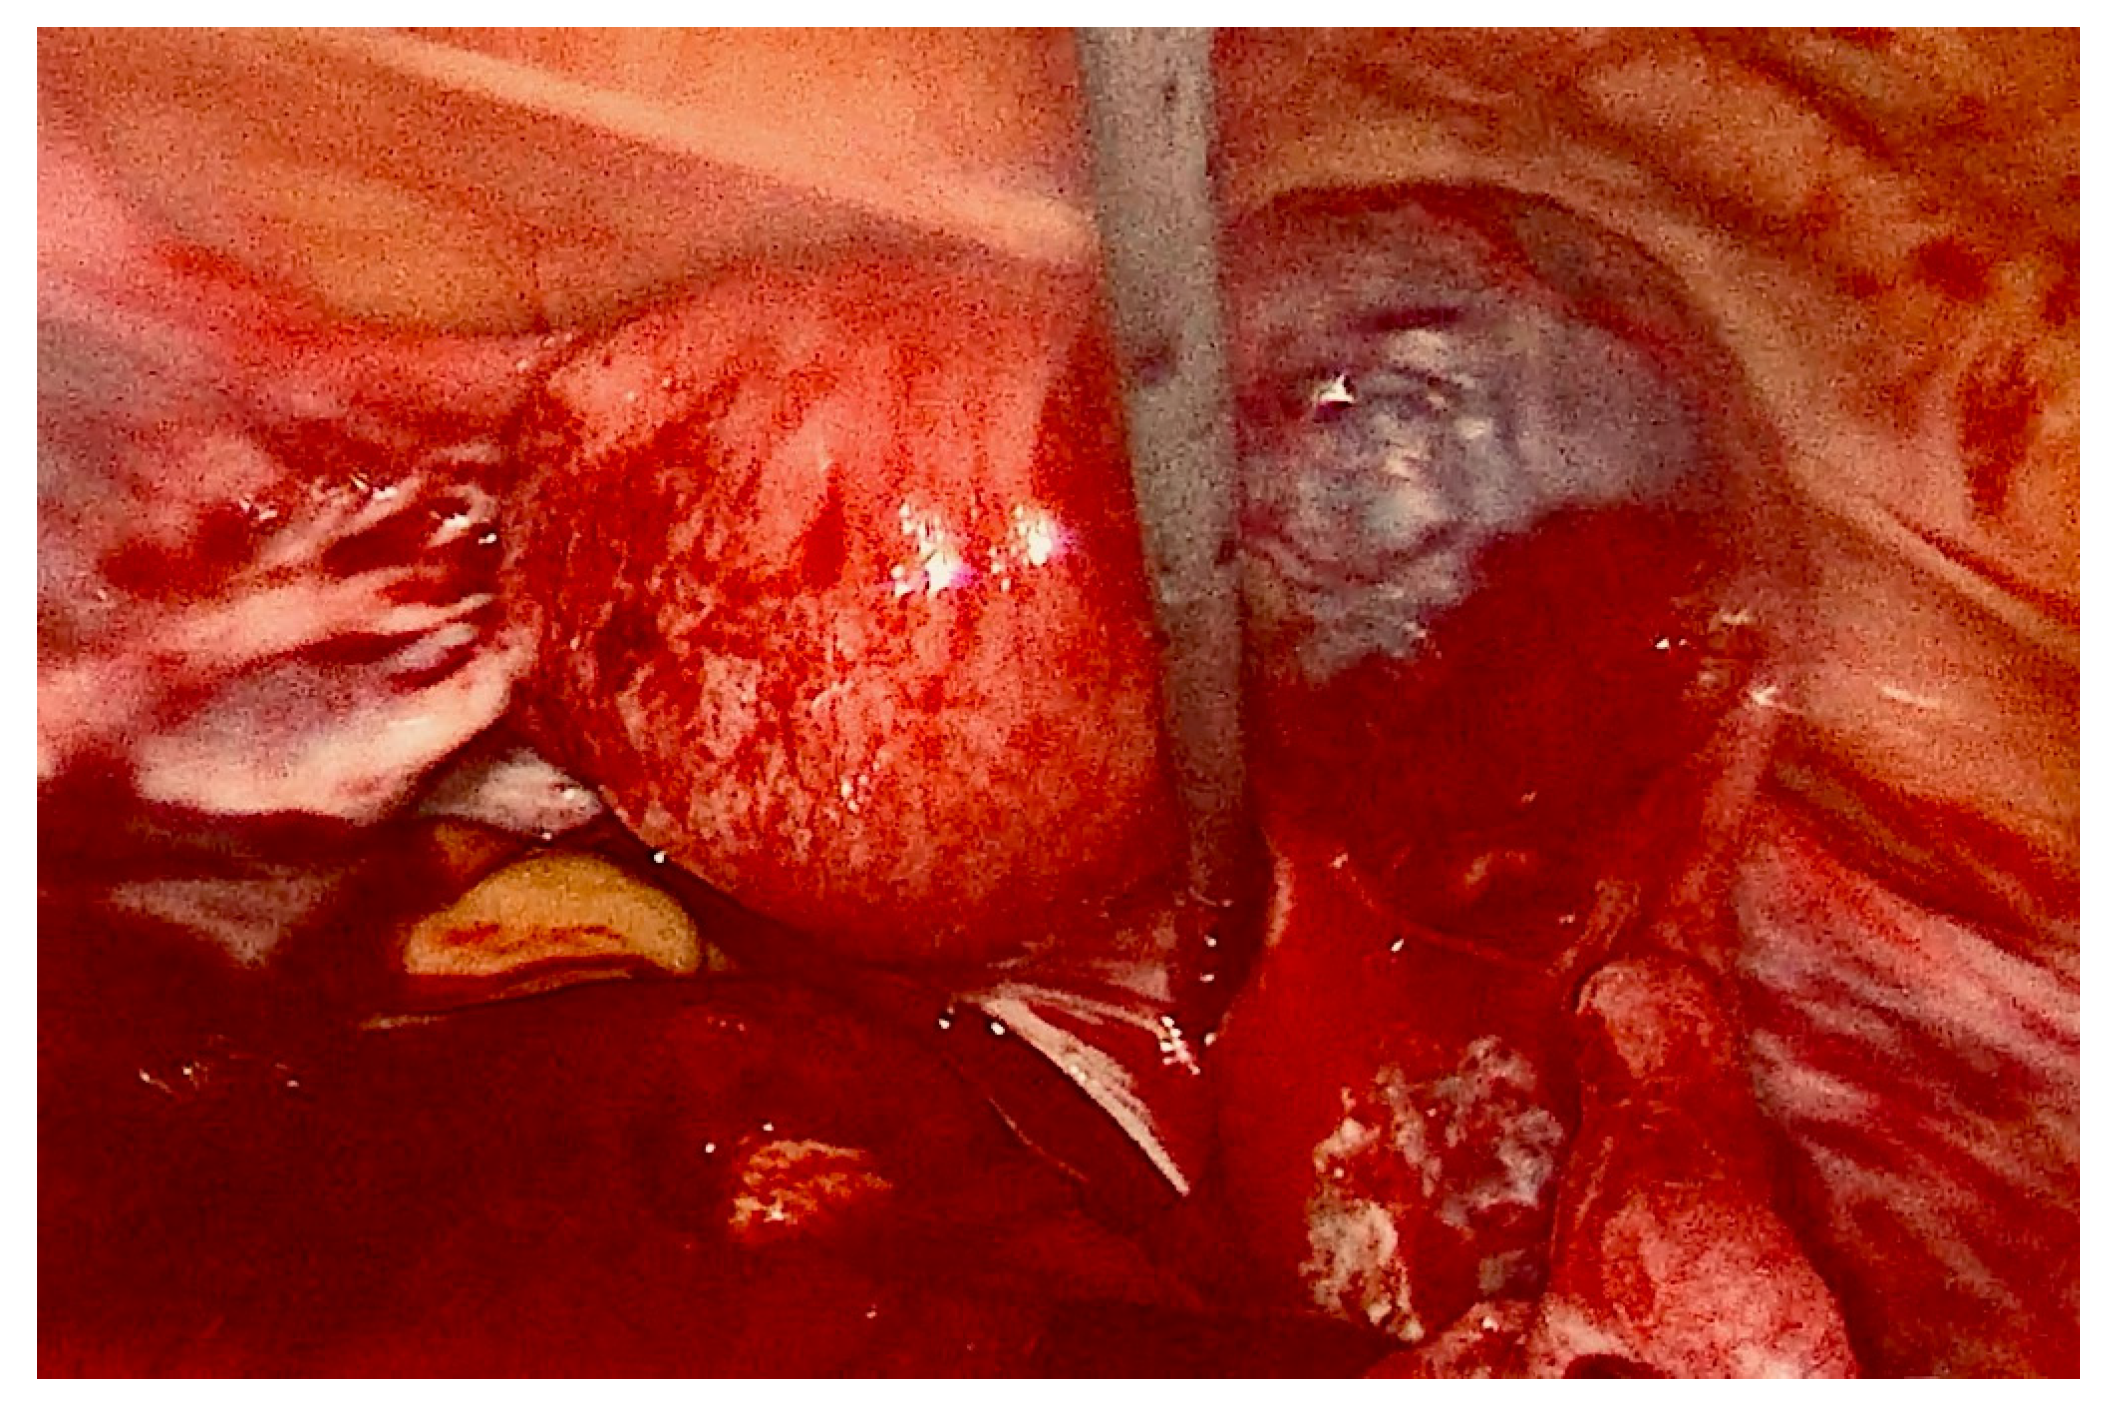

2. Case Presentation